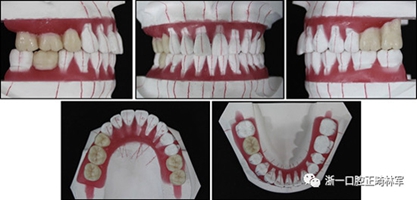

完成診斷性設(shè)計后,治療后穩(wěn)定的咬合是確定的(圖5)。進行治療之前,治療計劃和順序需要通過涉及正畸,牙周病和修復(fù)的多學(xué)科綜合治療方法加以確認(圖6)。牙周治療應(yīng)在正畸治療前完成。牙周疾病的治療采用全口潔治,上頜和下頜前牙區(qū)的刮治術(shù),以及下頜左側(cè)后牙區(qū)的翻瓣手術(shù)。休息3個月后,幾乎每個部位都實現(xiàn)了牙周袋深度縮小,探針出血幾乎沒有(表III)??刂蒲装Y后,開始正畸治療。在正畸治療期間定期進行牙周維護的復(fù)診檢查。

圖5. 治療計劃的診斷性設(shè)置

圖6. 治療計劃和應(yīng)用正畸學(xué),牙周學(xué)和修復(fù)學(xué)的跨學(xué)科綜合治療順序